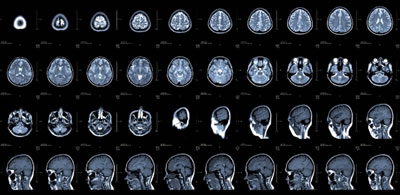

O cérebro, por toda a sua complexidade,

é um órgão que vem sendo cada vez mais estudado.

Mas a verdade é que ainda se sabe pouco sobre ele. Uma das teses